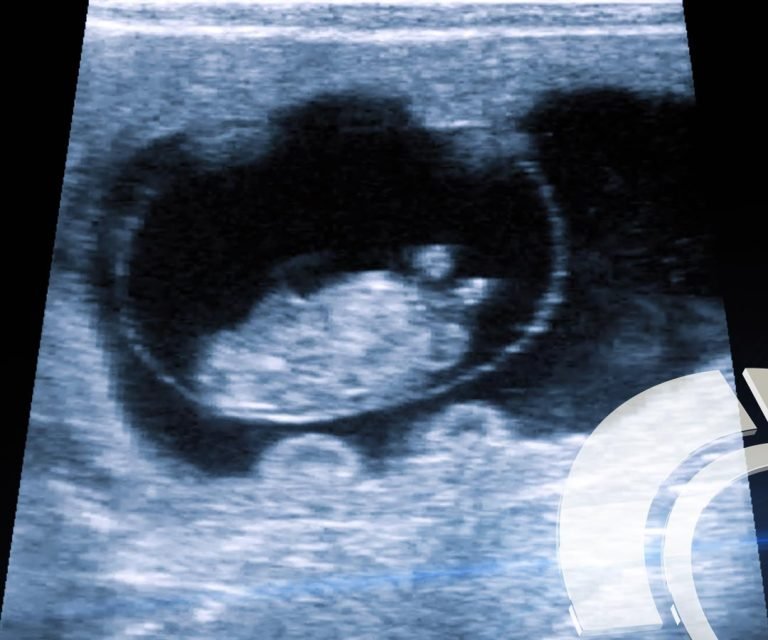

La ecografía o ultrasonografía es la técnica que utilizan veterinarios especializados como una herramienta para evaluar la composición carnicera en los animales vivos denominado Mérito de Carcasa; y en Reproducción se utiliza para el Diagnóstico temprano de Gestación, Sexado Fetal, determinación de Quistes Foliculares y Diagnóstico de Patologías.

El estudio de la composición y calidad carnicera de los animales de producción, el control de la Gestación y diagnóstico de patologías, es una de las tendencias actuales.

Esta Tecnología es también nombrada como Ultrasonido, es la técnica que utiliza las ondas de sonido y sus ecos, de forma tal que se hacen visibles las estructuras de un cuerpo.

Reproducción

- Determine preñez en vacas, 45 días antes que un tacto rectal. Determinación de la preñez a partir del día 24 pos-servicio en bovinos.

- Si Ud. insemina y luego repasa con toros, determine si la gestación es fruto del entore natural o artificial.

- Divida el rodeo por fechas de parición.

- Estudios utero-ováricos pre-servicio. Sexado fetal bovino a partir del día 60.

- Ecografías en machos, para determinar funcionalidad y diagnóstico en patologías externas e internas.